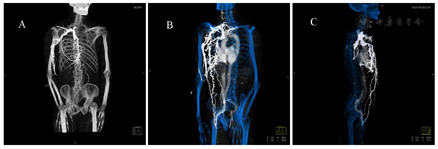

患者男,66岁,胸壁腹壁表浅静脉曲张半年,脸肿1个月余,随后行上腔静脉CT血管成像。

对比剂延扩张的胸壁以及腹壁表浅静脉,分别回流至双侧髂静脉,顺下腔静脉回流至心脏。其中奇静脉和肋间静脉也有扩张和对比剂充盈。上腔静脉中段显示局限性狭窄,接近闭塞,致使大量回流静脉扩张并逆流至髂静脉回流至心脏。

CT静脉血管成像能快速、多次连续采集图像,可以全面观察静脉阻塞的直接征象和继发征象。直接征象表现为管腔内充盈缺损,可以明确判断梗阻的部位、狭窄的程度;继发征象包括侧支循环形成、胸腔积液、头颈胸壁水肿等情况[3,4]。

总之,CT血管成像检查迅速、便捷、无创等优势受到临床一致认可,一次检查可以提供动脉、静脉、大范围血管侧枝形成等病变的详细信息,为临床进一步治疗带来帮助。